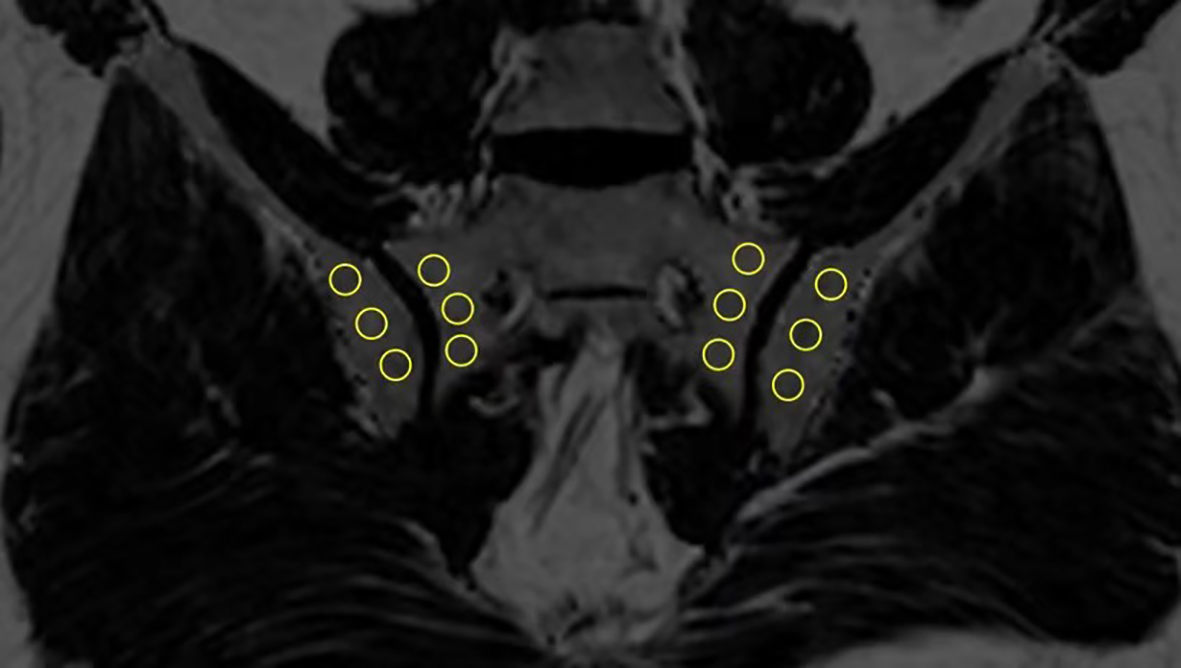

In order to estimate the fat fraction of each participant in the SIJs, the fat fraction maps were presented to each observer. Three consecutive slices most representative of the sacroiliac joint in the semi-coronal orientation were selected for the delineation of regions of interest (ROI). ROIs come in the shape of circles with sizes ranging from 10-40 mm2. Three ROIs were manually placed in the subchondral bone on both the left and right sacral side and iliac side (Figure 1). The overarching principle for ROI placement is that ROIs should be evenly distributed while capturing the extent of regional fat deposition. ROIs should stay clear of any erosion, blood vessel, cavity or obvious regional bone marrow edema. The mean PDFF values within the ROIs were generated automatically by the system.

Figure 1 Placement of ROIs in the subchondral area in the SIJs (ROI, regions of interest; SIJs, sacroiliac joints).